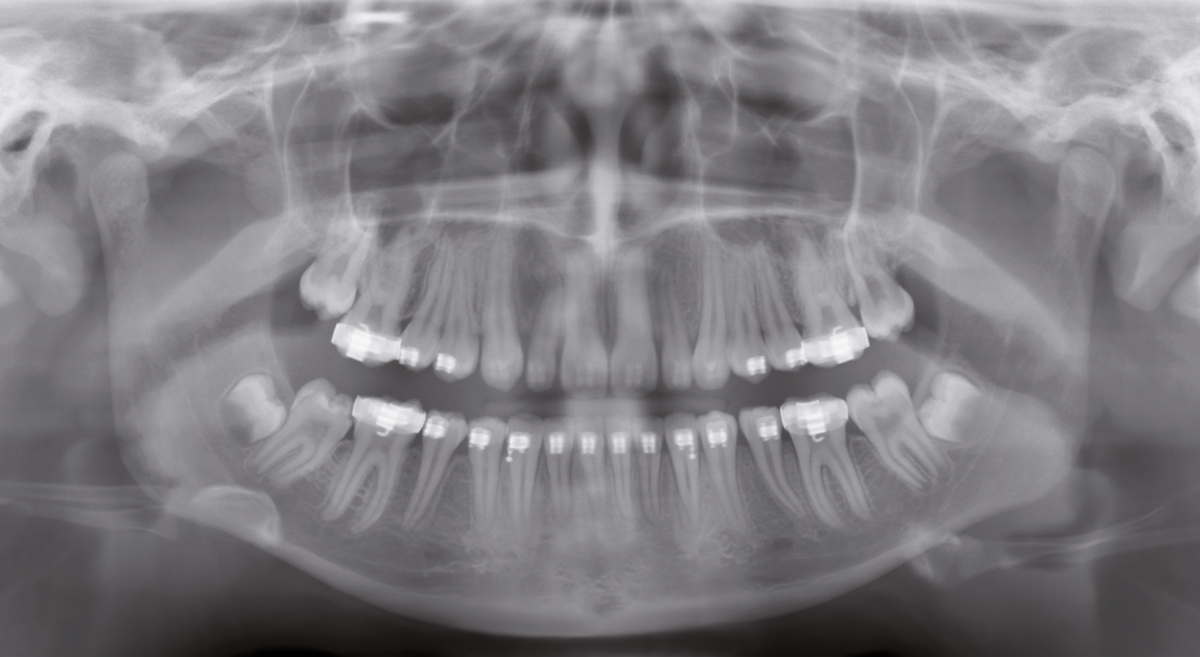

Sin márgenes alrededor de rellenos metálicos, sin contraste excesivo que podría, por ejemplo, llevar al diagnóstico incorrecto de la caries: el algoritmo del software innovador ASTRA mejora de forma significativa la calidad de las imágenes Ceph y panorámicas 2D.

El algoritmo de reconstrucción estructurada de forma anatómica (ASTRA) genera imágenes estructuradas con contrastes más altos sin el aspecto de artefactos de borde. ASTRA es un plugin del nuevo software SIDEXIS 4 y garantiza un detalla preciso sin artefactos. Esto permite que los usuarios realicen diagnósticos rápidos y confiables.

Márgenes negros alrededor de los rellenos metálicos

Artefactos problemáticos

Contraste en una imagen estructurada